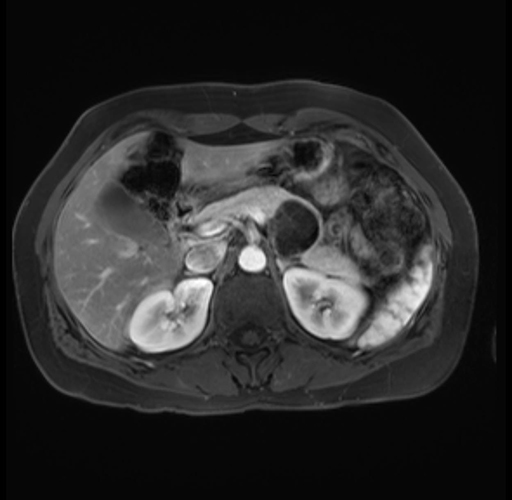

Imaging Analysis

Look through the patient's CT scan to identify any areas of concern for the necessary procedure.

Based on your CT findings, which issue(s) are present and would give reason for "planned slowing down moment(s)" in this case?